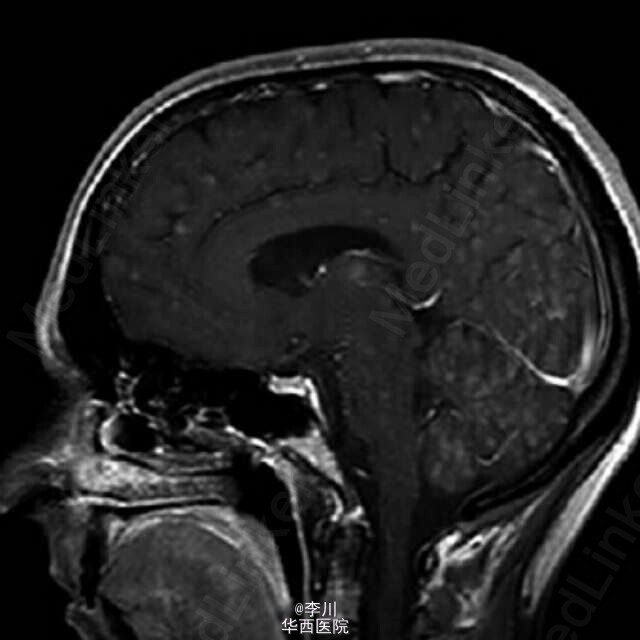

患者女性,38 岁,肺腺癌,年吸烟量 15 包。胸部 CT 表现右上肺脊柱旁肿物。胸膜活检病理证实为乳头状肺腺癌。头颅磁共振显示除灰质外,大脑皮质,基地核和丘脑 粟粒状结节。可以媲美粟粒性肺结核Dziadziuszko K, Szurowska E, Pienkowska J, et al. Miliary Brain Metastases in a Patient with ROS1-Rearranged Lung Adenocarcinoma: A Case Report[J]. Journal of Thoracic Oncology, 2014, 9(5): e34-e36.